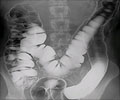

Colorectal cancer is the second leading cause of cancer-related deaths. However, the disease is preventable if detected in the precancerous stages.

Current risk stratification methods for colorectal cancer screening recommendations are relatively crude, based on age and family history alone. No family history of the disease? Start colonoscopies at age 50. Have an immediate relative who had colorectal cancer? Screen at age 40.

But these methods are likely missing many at risk, Peters said. Eighty percent of those with colorectal cancer have no known family history. And, unlike some, it's a cancer where screening and prevention are tightly linked - colonoscopies can catch premalignant lesions, and if those lesions are removed, the patient is spared from ever developing cancer.